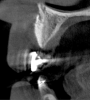

Fig 3. Tomographic images revealed a tridimensional defect extending to the apical third of teeth Nos. 6 and 8, a buccal bone dehiscence on tooth No. 5, and associated thin labial plates.

Figure 3

Tomographic images revealed a large tridimensional defect, with vertical and horizontal loss of bone extending to the apical third of teeth Nos. 6 and 8. Additionally, a buccal bone dehiscence was evident on tooth No. 5, and thin labial plates secondary to the orthodontic movement were present in several areas (Figure 3 and Figure 4).